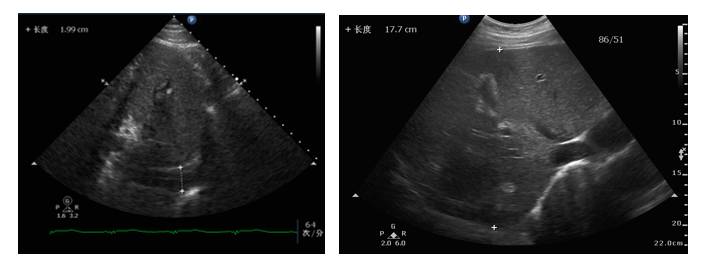

体循环淤血改善

循环有所改善

♥去甲肾上腺素:0.4ug—0.09ug/kg/min

♥乳酸:正常范围

♥心脏舒缩功能好转,循环灌注改善(无酸中毒,乳酸正常)